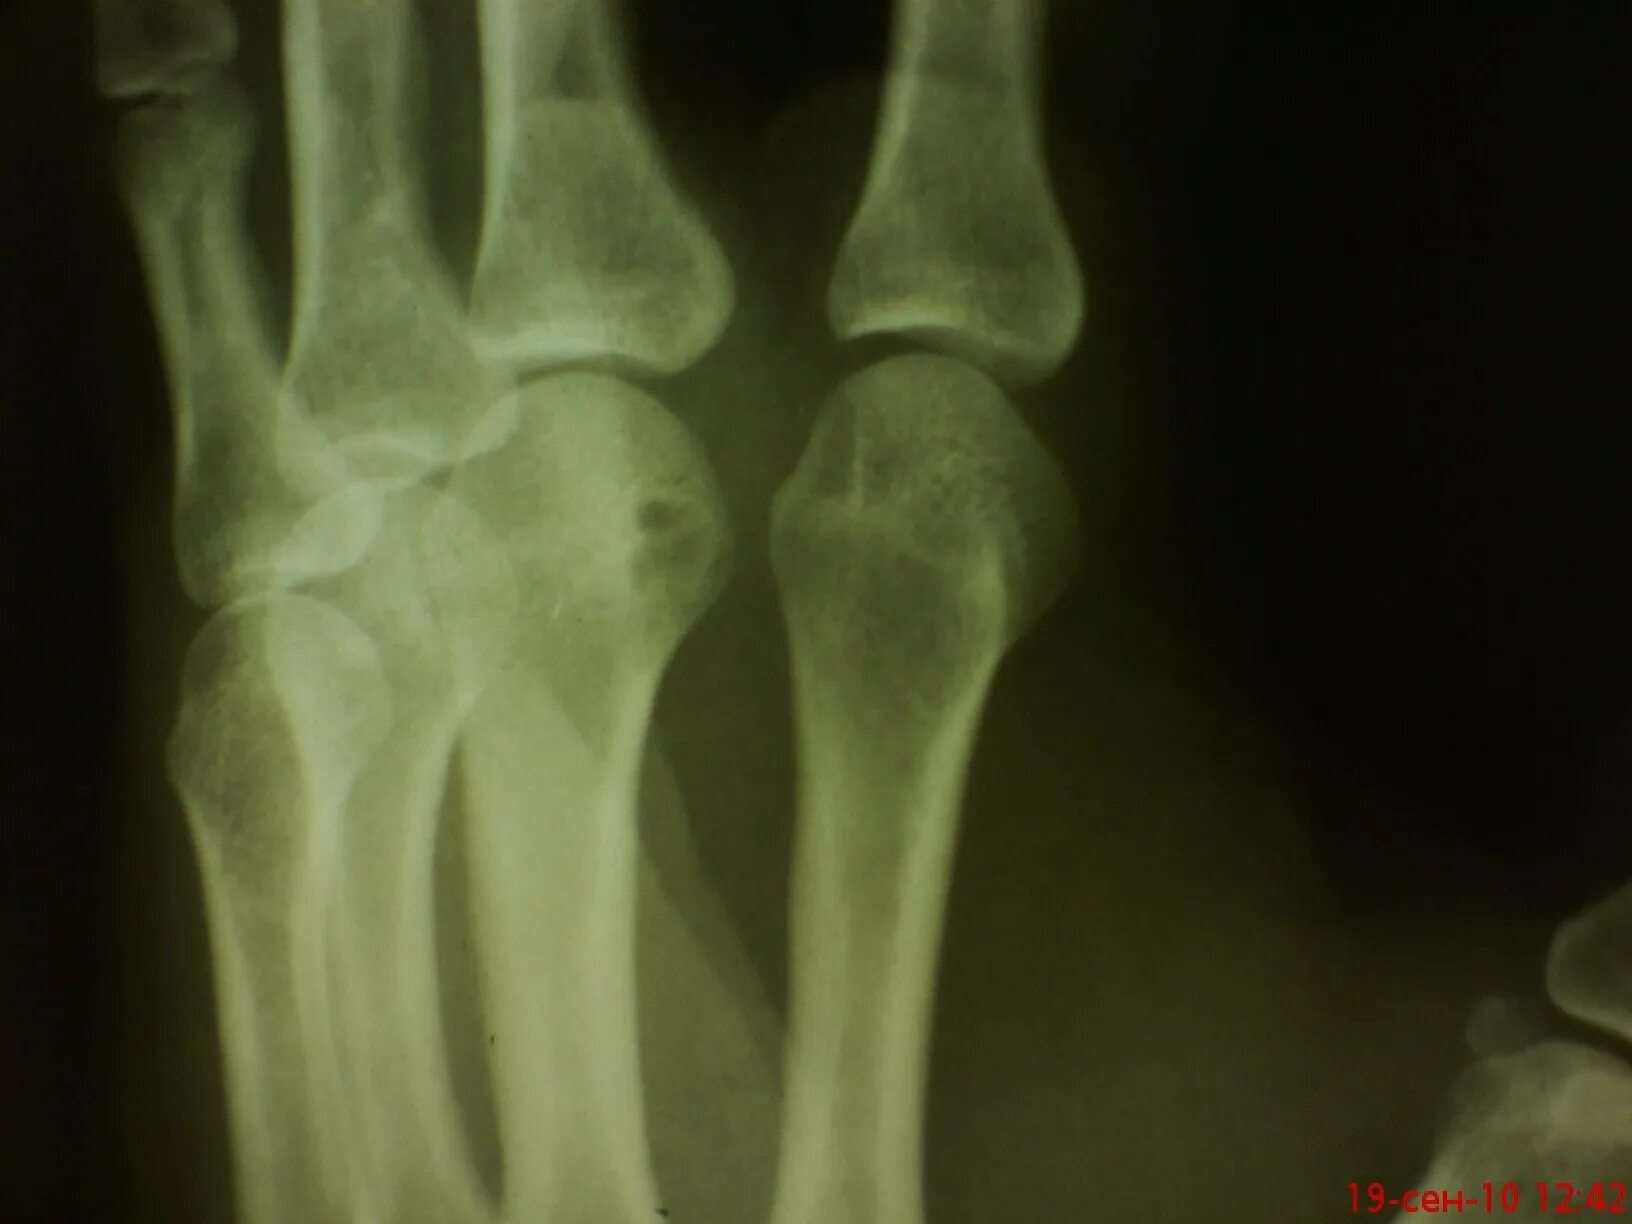

Растяжение лучезапястного сустава мкб